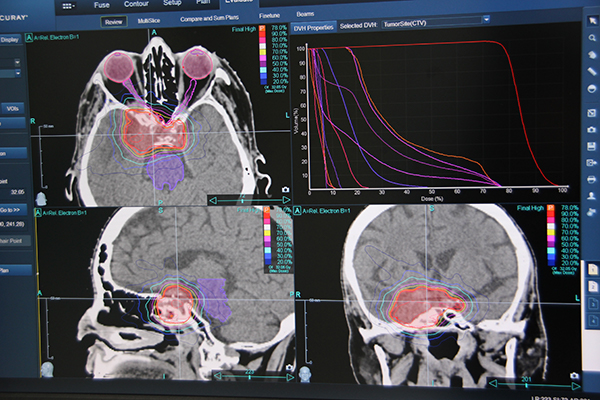

アキュレイプレシジョンは,トモセラピー,ラディザクトの治療計画に加え,新しくサイバーナイフの治療計画も可能になったことをアピールした。両方の治療機器を有する施設では,アキュレイプレシジョンをどちらの治療計画にも利用できるため,治療状況によって柔軟に使い分けることができる。両方の治療計画画面の画面分割方法やボタンの配置など,ユーザーインターフェースを類似させることで,操作性の統一も図った。なお,トモセラピー,ラディザクト対応の既設システムに対しても,バージョンアップによりサイバーナイフに対応する。

アキュレイプレシジョンの特長の一つが,頭蓋内,頭頸部,男性骨盤内を対象にした“AutoSegmentation”機能である。従来は,重要臓器の輪郭作成に膨大な時間を要していたが,AutoSegmentationではGPUを応用することで,計画用CT画像を取り込むと設定された重要臓器の輪郭を自動で囲むことができる。例えば,頭部では1分程度で輪郭作成が可能で,治療計画の作業時間が大幅に短縮可能となる。

また,アキュレイプレシジョンは,“アダプティブセラピープログラム”と“リトリーメントプログラム”を標準搭載した。アダプティブセラピープログラムは,治療を進める中で腫瘍が縮小するなど,オリジナルの治療計画から腫瘍の形が変わった場合に,形状変形を自動認識しアラートを表示する。治療計画の検証ツールを装備しており,実行ずみの治療や輪郭変形を含めて評価し,治療計画の立て直しの必要性を示すことができ,経時的に変化する状況に計画を適応させることで,不要な線量を照射することのない適切な治療の実施を支援する。

リトリーメントプログラムは,治療中,または治療歴のある患者に対して,新しい治療計画を作成する際に,以前の線量データを踏まえた上で線量分布を計算することができる。他社製も含めたほかのシステムのデータもインポート可能で,放射線治療の安全性を高める。

アキュレイプレシジョンの治療計画画面

重要臓器を自動で抽出する“AutoSegmentation”機能

小児に対する全身照射(TBI)の治療計画画面